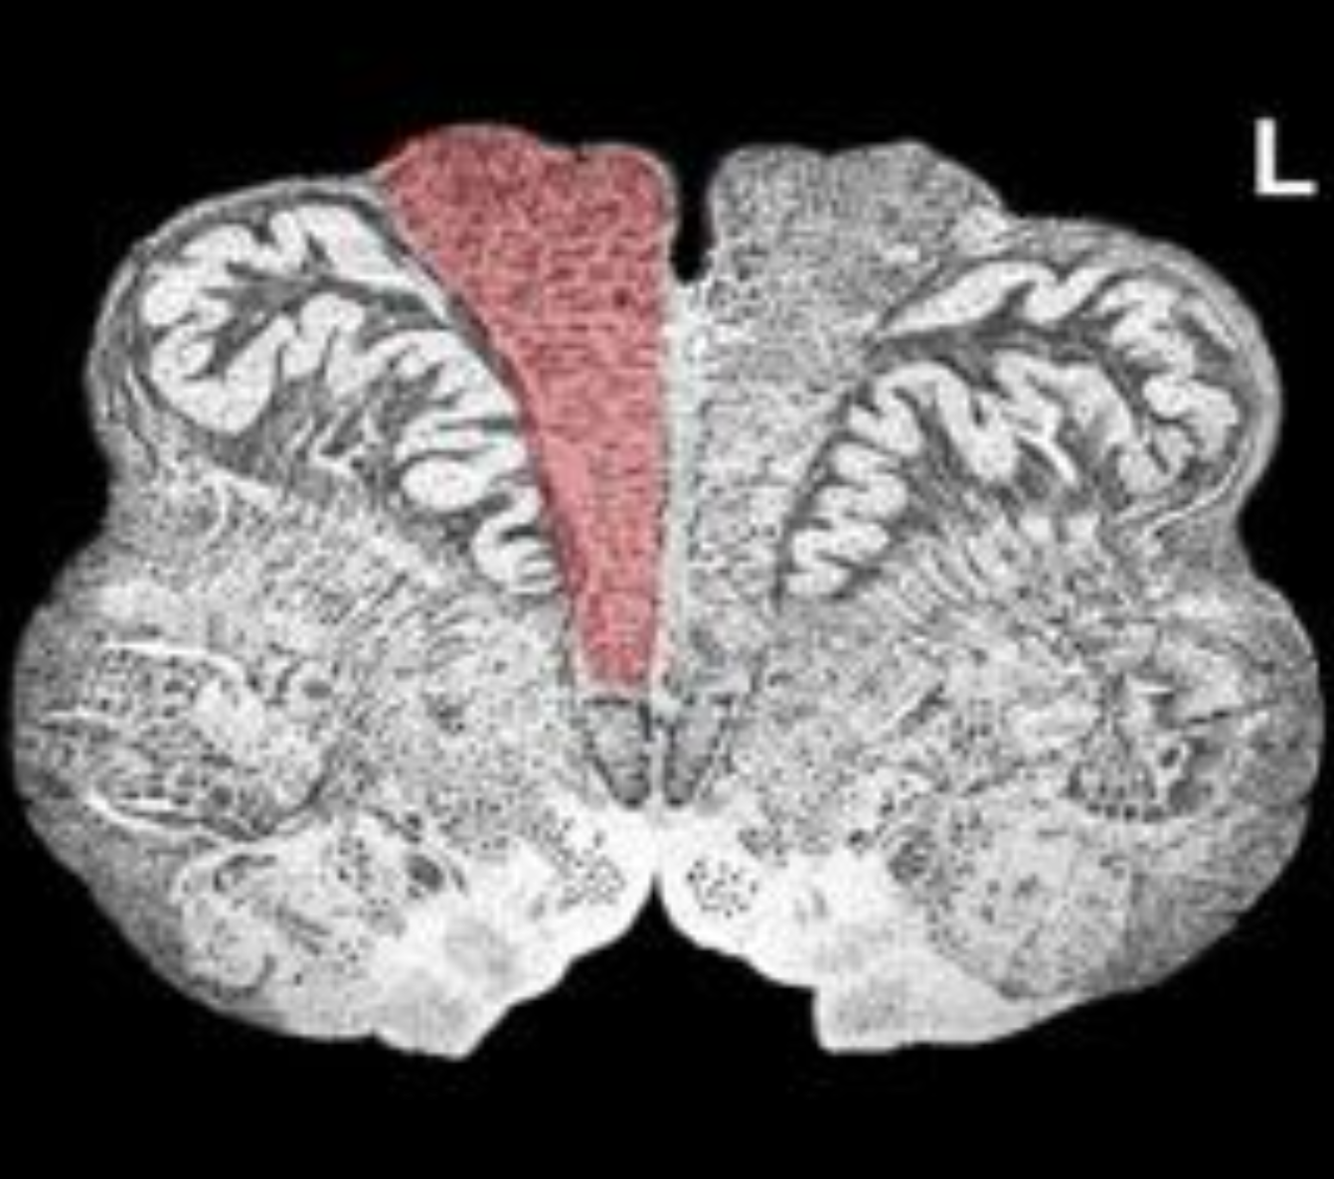

What is the name/location/results of the condition caused by a lesion in the shaded area?

Medulla at mid olive

Alternating Hypoglossal Hemiplegia and destruction of the ipsilateral Medial Lemniscus

lesion at Medulla at mid olive with dorsal extension